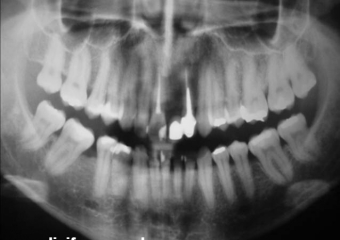

Raio X final